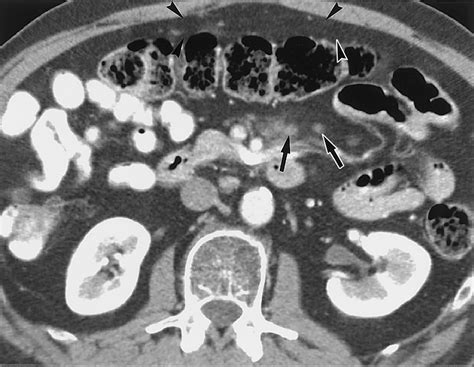

Understanding the intricacies of fat stranding on CT is crucial for radiologists and healthcare professionals who interpret computed tomography (CT) scans. Fat stranding refers to the presence of increased fat density in the soft tissues, often indicative of inflammation or injury. This phenomenon is particularly important in abdominal and pelvic imaging, where it can provide valuable insights into various pathological conditions.

Fat stranding on CT scans appears as areas of increased attenuation within the fatty tissue, typically seen as streaky or hazy densities. This finding is often associated with inflammation, infection, or trauma. The increased density is due to the infiltration of inflammatory cells and edema into the fatty tissue, altering its normal radiolucent appearance.

• Mesentery: Fat stranding in the mesentery is often associated with conditions like mesenteric ischemia, pancreatitis, or inflammatory bowel disease.

• Omentum: Omental fat stranding can be seen in conditions such as appendicitis, diverticulitis, or ovarian torsion.